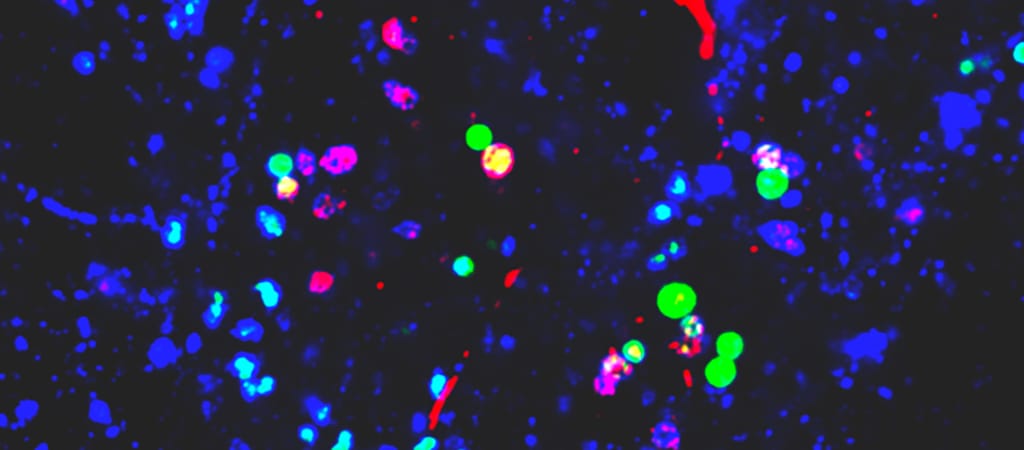

Egy új áttekintés pedig most pontos képet fest arról, hogy mennyire. A Kaliforniai Egyetem, San Francisco (UCSF) kutatói szerint ugyanis a levegőben, élelmiszerekben és vízben lévő szintetikus részecskék termékenységi problémákhoz, vastagbélrákhoz és csökkent tüdőfunkcióhoz vezethetnek.

A három, emberekkel végzett vizsgálat 2022 és 2024 között zajlott Törökországban, Iránban és Kínában. Egy a magzatvízben, egy az orrváladékban, egy másik pedig a méhlepényben bukkant mikroműanyagokra – derül ki az Environmental Science & Technology tudományos folyóiratban publikált megállapításokból.

A UCSF tudósai állítják: elsők között elemezték a mikroműanyagokra vonatkozó egészségi bizonyítékok „minőségét és erősségét”. Ami pedig a spermiumok minőségét, a bélrendszer immunválaszát illeti, a szakemberek úgy vélik, a bizonyítékaik „magas minőségűek”.

Az állatkísérletek során a mikroműanyagok hatására jelentős elváltozásokat figyeltek meg a vastagbélben, a spermiumok minőségében és a tüdőfunkciók terén is. A bizonyítékok mentén a kutatók sürgetik a szabályozókat és a döntéshozókat, hogy cselekedjenek, és tegyenek lépéseket annak érdekében, hogy csökkenjen az emberek mikroműanyag-kitettsége.